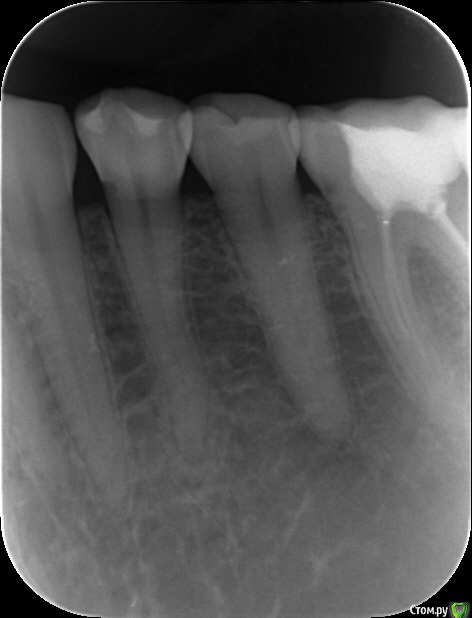

Прилагаю два снимка. От 18 июля, это когда обнаружили повторно кариес. От 9 августа - после всех пломбировок. На июльском снимке хирург (ходила отдельно со снимком на консультацию) диагностирует расширение периодонтальной щели. Другие врачи не видят!!! На августовском снимке щель уже не видна, она что могла самоизлечиться?

Есть ли фиброзный периодонтит? Удалять нерв? Чем опасно расширение периодонтальной щели? Нерв рекомендовал удалить по снимку хирург, но он сам терапевтическое лечение не оказывает, а рекомендуемый им врач утверждает, что нет показаний для удаления нерва, периодонтальную щель не видит. СПАСИБО!